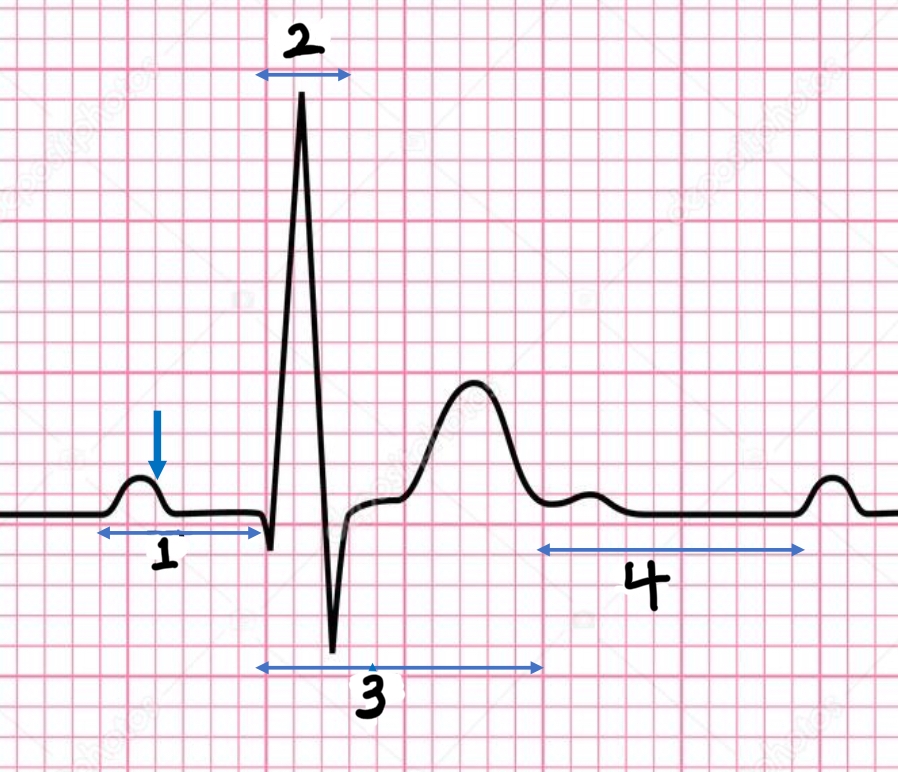

P wave

atrial depolarization

Precedes atrial contraction

QRS complex

ventricular depolarization

Precedes ventricular contraction

T wave

ventricular repolarization

PR interval

Name #1

QRS interval

Name #2

QT interval

Name #3

TP interval

Name #4

PR interval

time from beginning of the P wave to the beginning of the QRS complex

QRS interval

Time from beginning of the QRS complex to the end of the QRS complex

QT interval

Time from beginning of QRS complex to the end of the T wave

TP interval

Time from end of T wave to the beginning of P wave